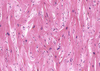

Identify

Serous Atrophy of fat